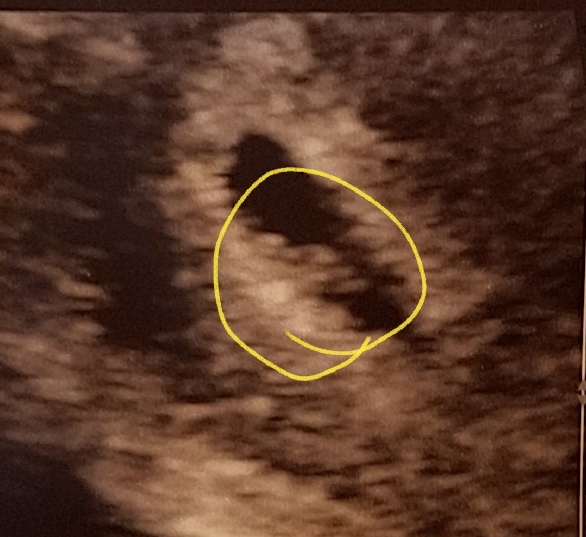

Me: 30 | DH: 34 | DSS: 14 | DS: 4PG #2, EDD 10/12/2023

Me: 30 | DH: 34 | DSS: 14 | DS: 4

PG #2, EDD 10/12/2023